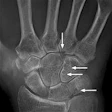

Musculoskeletal Radiology: Page 74